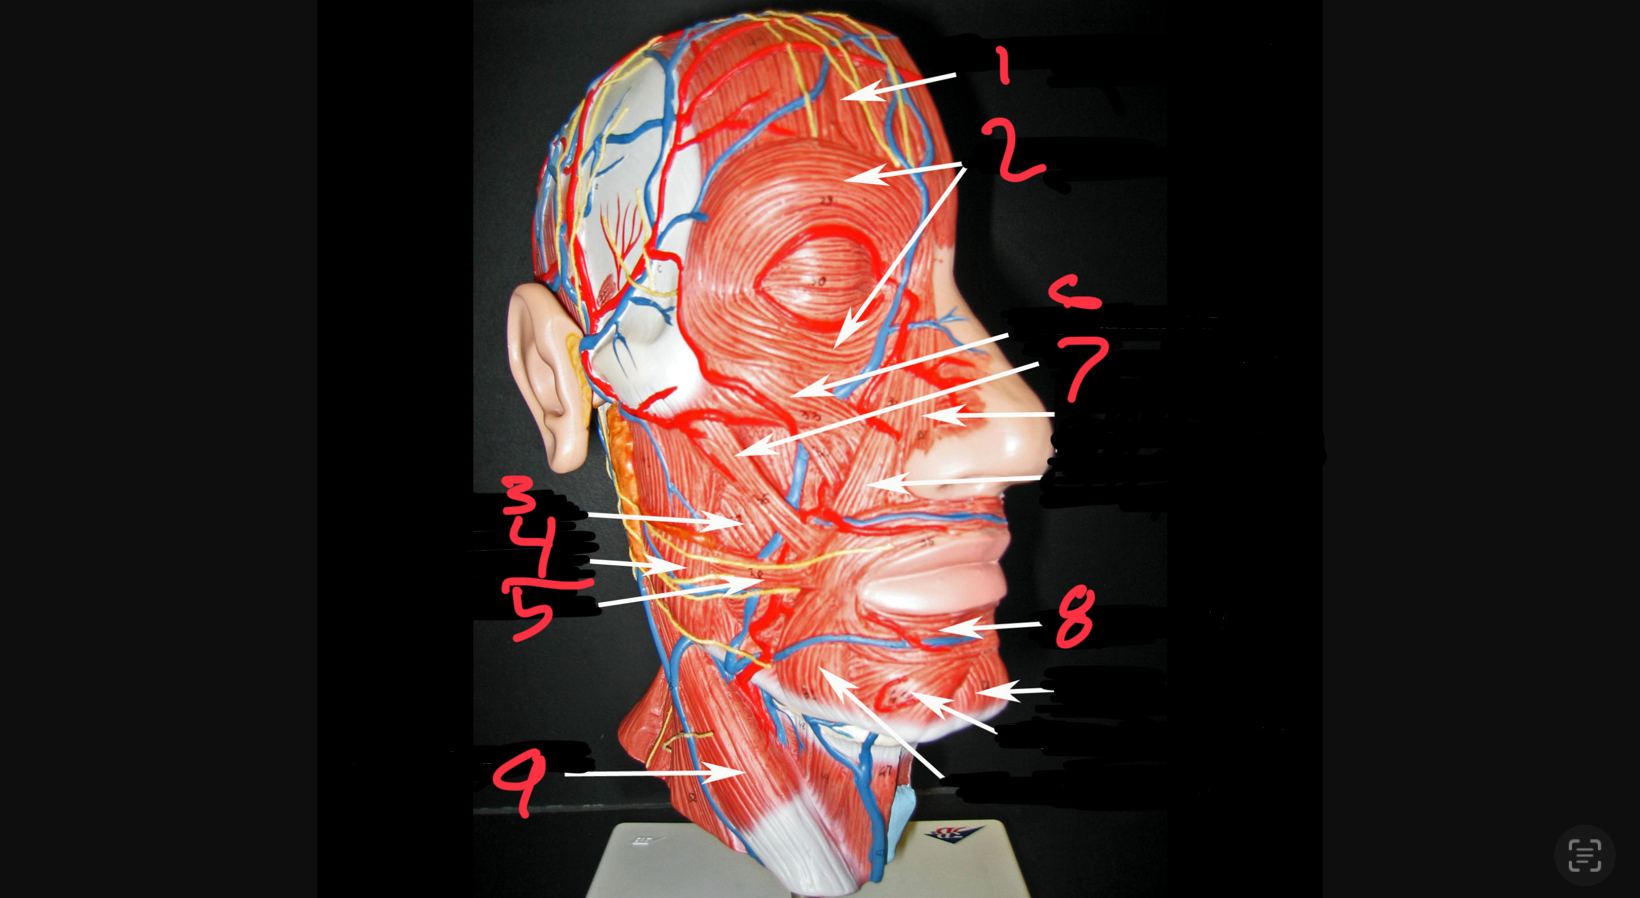

what #1

occipitofrontalis (frontal belly)

what is #2

orbicularis oculi

what is #3

buccinator

what is #4

masseter

what is #5

risorius

what is #6

zygomaticus minor

what is #7

zygomaticus major

what is #8

orbicularis oris

what is #9

sternocleidomastoid